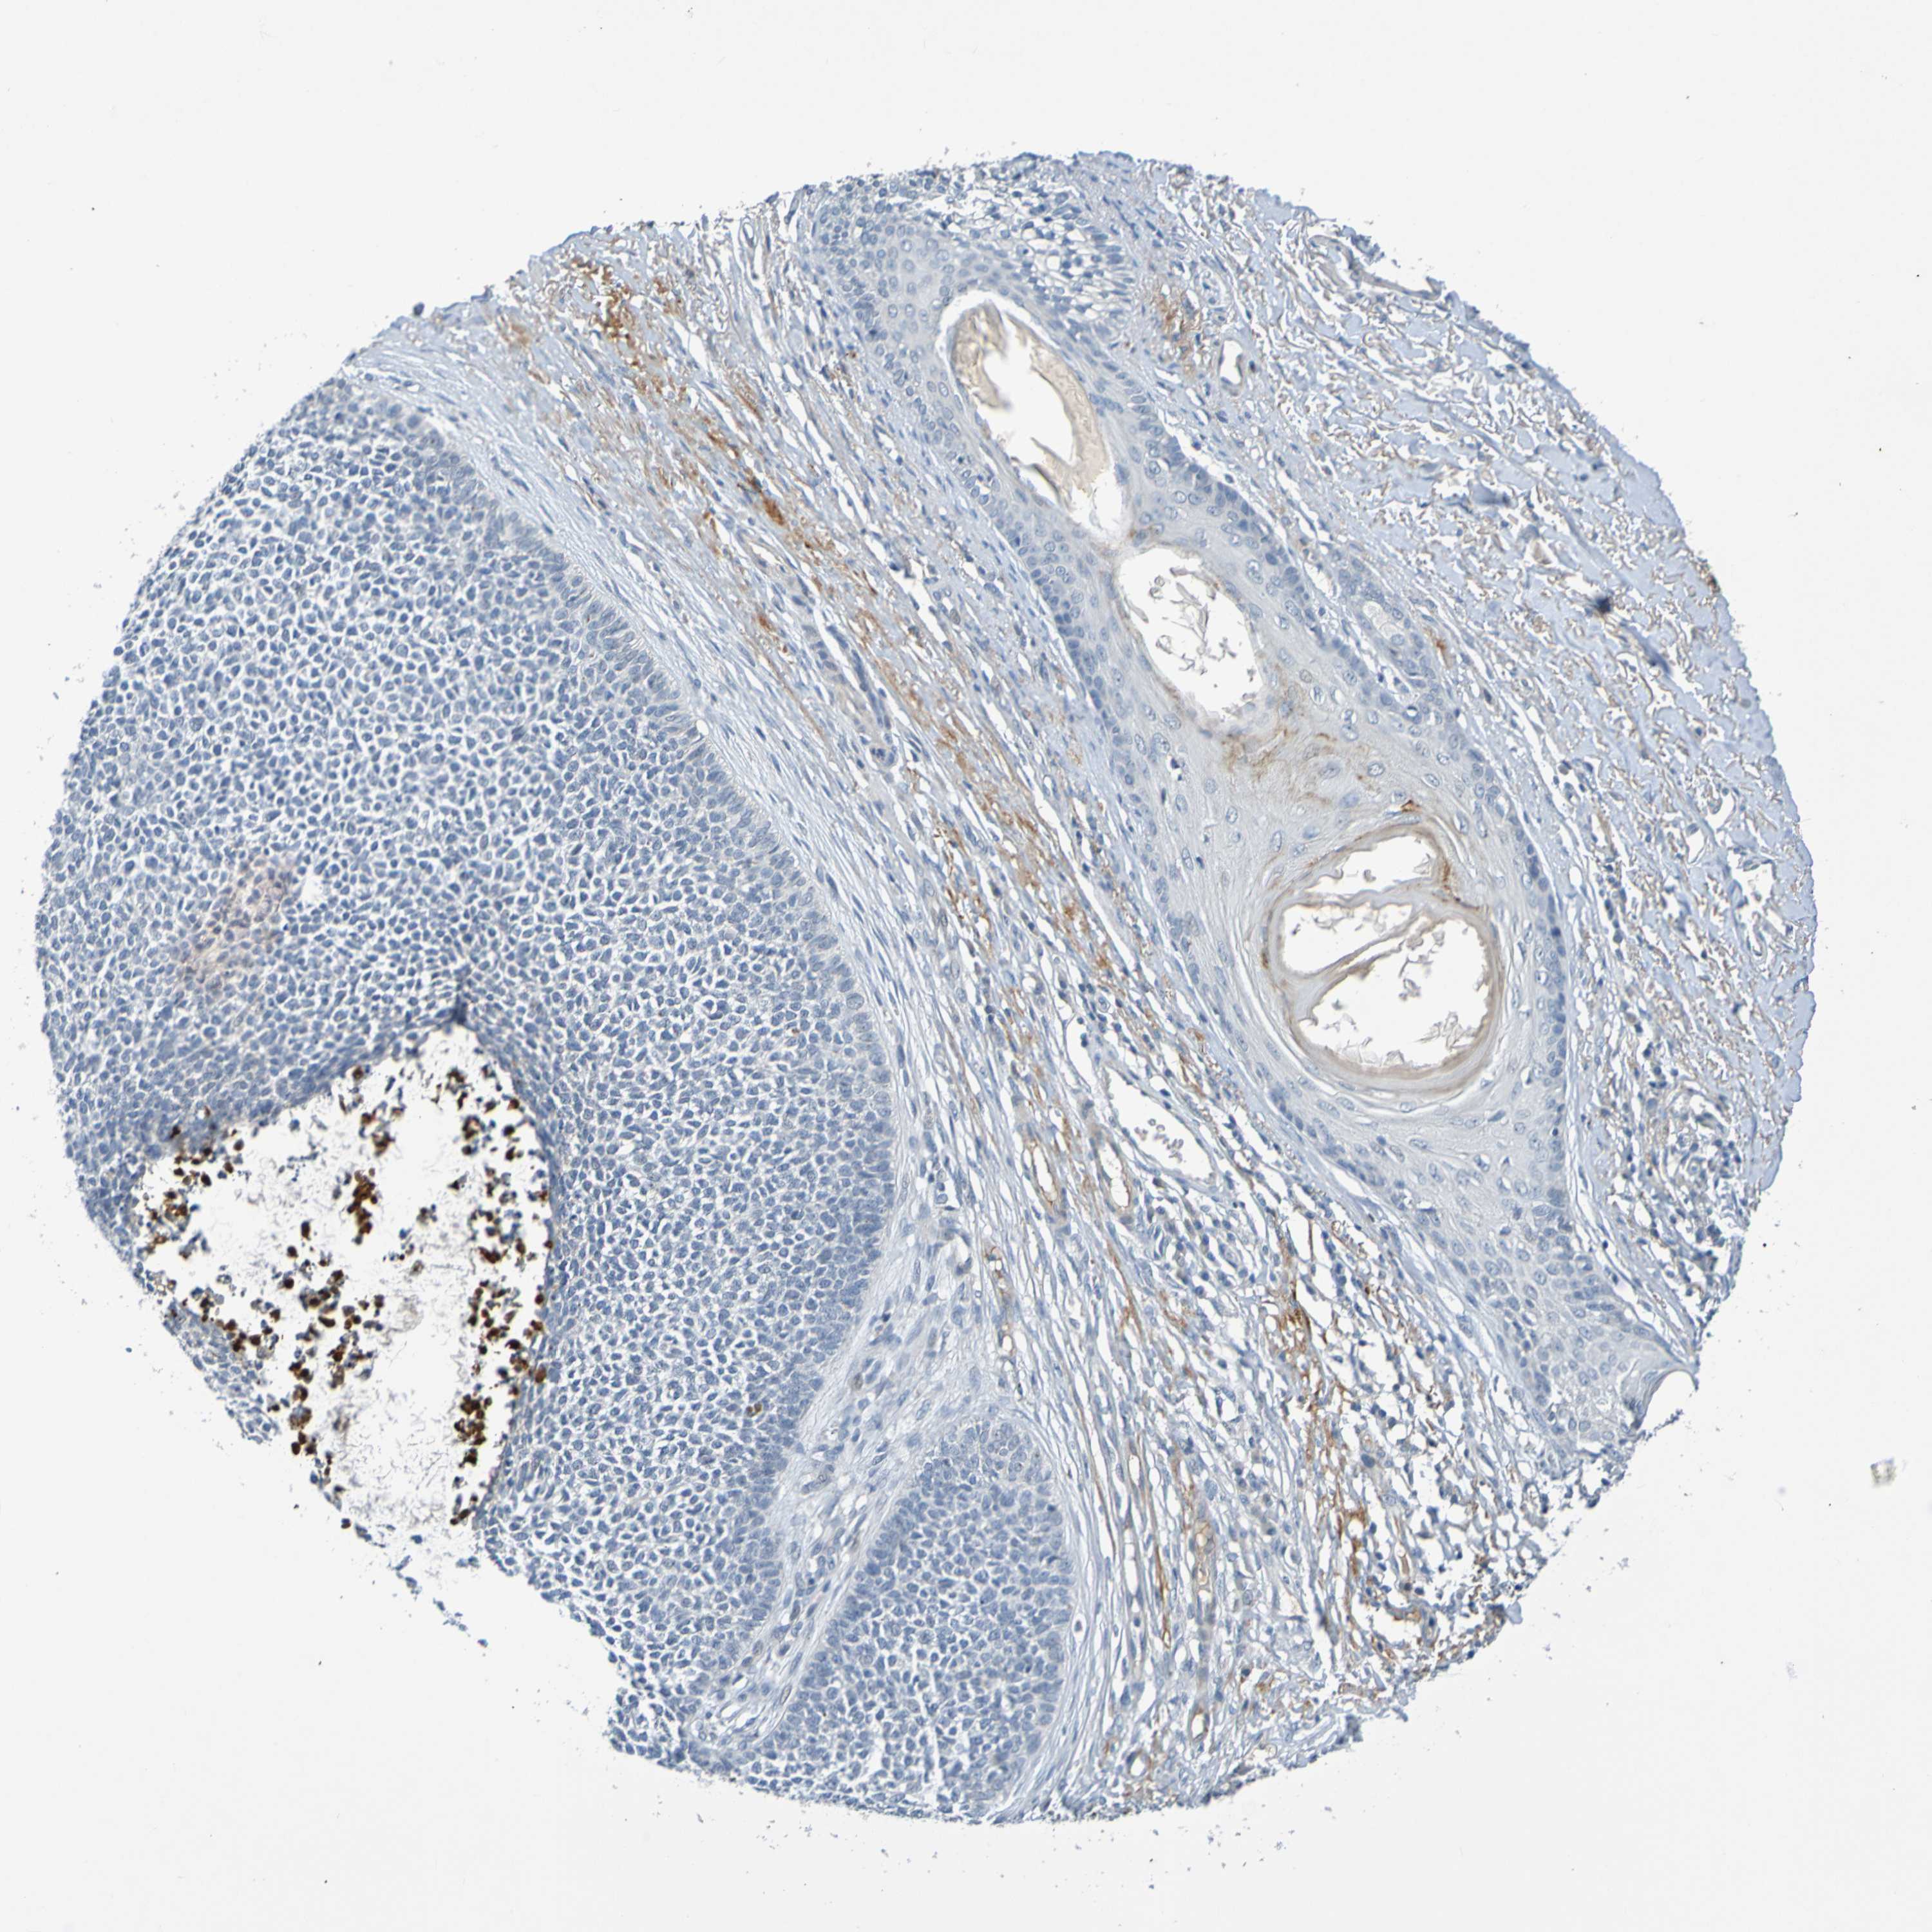

SKIN CANCER - Protein expressioni

A mouse-over function shows sample information and annotation data. Click on an image to view it in a full screen mode. Samples can be filtered based on level of antibody staining by selecting one or several of the following categories: high, medium, low and not detected. The assay and annotation is described here.

Antibody stainingi

Antibody staining in the annotated cell types in the current human tissue is reported as not detected, low, medium, or high, based on conventional immunohistochemistry profiling in selected tissues. This score is based on the combination of the staining intensity and fraction of stained cells.

Each image is clickable and will lead to virtual microscopy that enables deeper exploration of all samples and also displays staining intensity scores, fraction scores and subcellular localization as well as patient and tissue information for each sample.

Antibody HPA071391

Antibody CAB013120

Basal cell carcinoma

Squamous cell carcinoma, NOS